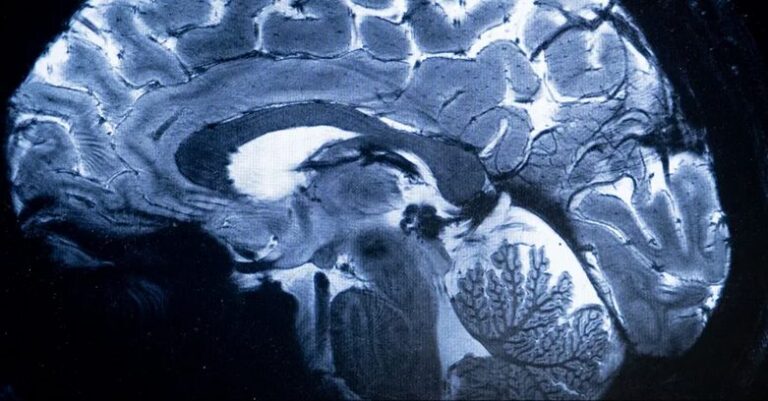

الإصابات الشديدة بكورونا يمكن أن تؤدي إلى التهاب في الدماغ صحة هذا ما يفعله فيروس كورونا بجذع الدماغ الذي “يتحكم في الحياة” by admin 8 أكتوبر، 2024 written by admin 8 أكتوبر، 2024 205 سكاي نيوز عربية / ترجمات – أبوظبي رغم تراجع حدة وباء كورونا، لا يزال العلماء يجرون دراسات للتعرف أكثر على الفيروس الذي شل العالم لفترة، وكشف تأثيره على أجساد المصابين به. وفي أحدث ضرر اكتشف لمرض “كوفيد 19“، قال باحثون إن الإصابات الشديدة به يمكن أن تؤدي إلى التهاب في “مركز التحكم” داخل الدماغ، مما يسبب تلفا قد يفسر ضيق التنفس والتعب والقلق الذي يلازم بعض المرضى لفترات طويلة. وأظهرت عمليات مسح التصوير بالرنين المغناطيسي لـ30 مريضا أدخلوا المستشفى بسبب “كوفيد 19” في وقت مبكر من الوباء قبل نشر اللقاحات، علامات على التهاب في جذع الدماغ، وهو جزء صغير لكنه بالغ الأهمية لأنه يتحكم بوظائف الجسم التي تدعم الحياة، مثل التنفس والنبض وحركة الدم. وتشير عمليات المسح إلى أن الإصابات الشديدة بفيروس كورونا يمكن أن تثير رد فعل مناعيا يؤدي إلى التهاب جذع الدماغ، مما يسبب أعراضا يمكن أن تستمر لأشهر بعد خروج المرضى من المستشفى، وذلك حسب الدراسة المنشورة في صحيفة “برين” العلمية. وقالت عالمة الأعصاب في جامعة كامبريدج البريطانية المؤلفة الرئيسية للدراسة الدكتورة كاتارينا روا: “حقيقة أننا نرى تشوهات في أجزاء الدماغ المرتبطة بالتنفس تشير بقوة إلى أن الأعراض طويلة الأمد هي تأثير للالتهاب في جذع الدماغ بعد الإصابة بـ(كوفيد 19)”، وذلك في تصريحات نشرتها صحيفة “غارديان” البريطانية. وأجريت الدراسة قبل أن يكتشف الباحثون والأطباء ما أطلقوا عليه لاحقا اسم “كوفيد طويل الأمد“، وهو مرض مزمن بعد الإصابة بفيروس كورونا يعتقد أنه يؤثر على عشرات الملايين على مستوى العالم. ويبلغ الكثير من المصابين بكوفيد طويل الأمد عن ضيق في التنفس وتعب عام في الجسد لعدة أشهر، مما يزيد من احتمال أن يكون التهاب الدماغ وراء هذه الأعراض. وأضافت روا: “لم ندرس الأشخاص المصابين بكوفيد طويل الأمد، لكنهم غالبا ما يعانون تأثيرات طويلة الأمد من ضيق التنفس والتعب، التي تشبه الأعراض التي عانى منها الأشخاص المتأثرون بشدة بعد 6 أشهر من دخولهم المستشفى”. وتابعت: “هذا يقودنا إلى طرح السؤال: هل يعاني الأشخاص المصابون بكوفيد طويل الأمد أي تغييرات في جذع الدماغ؟”. واستخدمت روا وزملاؤها أجهزة تصوير بالرنين المغناطيسي قوية لفحص أدمغة المرضى، وكشفت هذه الأجهزة عن تفاصيل كافية لرؤية الالتهابات والتشوهات الدقيقة في أنسجة جذع الدماغ، علما أن جميع المرضى أدخلوا إلى المستشفى بسبب إصابات شديدة بفيروس كورونا قرب بداية الوباء. وسلطت الفحوصات الضوء على التشوهات المرتبطة بالالتهاب في أجزاء متعددة من جذع الدماغ، التي ظهرت بعد أسابيع من دخول المرضى إلى المستشفى، وكان الضرر لا يزال واضحا في عمليات المسح بعد أكثر من 6 أشهر. وقد يساهم تلف جذع الدماغ أيضا في مشاكل متعلقة بالصحة العقلية، التي يواجهها البعض بعد الإصابة بـ”كوفيد 19″، ومن بين المرضى في الدراسة كان لدى أولئك الذين يعانون أعلى مستويات التهاب جذع الدماغ أشد الأعراض الجسدية جنبا إلى جنب مع أعلى مستويات الاكتئاب والقلق. وقال بول مولينز أستاذ التصوير العصبي بجامعة بانغور في ويلز: “بينما لا تثبت هذه الدراسة بشكل قاطع أسباب كوفيد طويل الأمد، فإنها تشير بإصبع الاتهام إلى أحد الأسباب المشتبه بها المحتملة لبعض الأعراض التي يعانيها المرضى”. وأضاف: “ليس من الواضح أن هذا قد يفيد في طرق العلاج المحتملة لكوفيد طويل الأمد، لكنه ربما يشير إلى الحاجة للتعامل مع الالتهابات أثناء الإصابة الأولية بفيروس كورونا”. 0 comment 0 FacebookTwitterPinterestEmail admin previous post كلمة نعيم قاسم “الباردة”.. غموض وأسئلة متزايدة حول حزب الله next post نتنياهو يؤكد اغتيال صفي الدين: قتلنا نصر الله وخليفته وخليفة خليفته You may also like ماذا نعرف عن فيروس إيبولا… 10 أسئلة 21 مايو، 2026 (8 علامات) في الجسد تدل على إصابتك بسرطان... 21 مايو، 2026 فحوصات طبية تثبت إصابة مواطن كندي بـ”هانتا” 18 مايو، 2026 شركة أدوية يابانية تحذر من عقار بعد تسجيل... 17 مايو، 2026 أدوية اضطراب فرط الحركة قد تخفف من إجهاد... 15 مايو، 2026 دهون الموتى تدخل عالم التجميل عبر “حشوة الزومبي” 14 مايو، 2026 الثياب البيضاء تحت النار: ممرضات لبنان في قلب... 13 مايو، 2026 حين يتحدّث العَرق… جسدك يكشف عن مرضك قبل... 12 مايو، 2026 اختراقان علميان يرسمان ملامح جديدة لعلاج السرطان 12 مايو، 2026 دراسة: علاج خلوي يمكنه السيطرة على فيروس نقص... 12 مايو، 2026